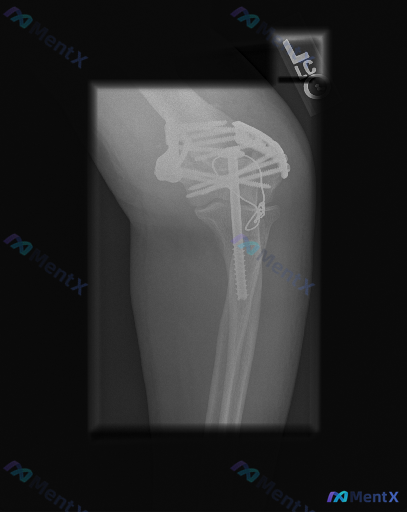

原以为是肩部X光,实际是左侧肘关节侧位片,有“L”左侧标记。

主要影像表现:

- 左侧肘关节肱骨远端、尺骨鹰嘴都是骨折内固定术后改变

- 肱骨远端看起来是双钢板固定,还有一枚长螺钉跨了髁间

- 尺骨鹰嘴有张力带样金属丝环绕

- 金属伪影很重,骨折线处骨痂生长看不太清楚,关节面也受遮挡

- 大体对线还行,没见明显脱位,软组织也没明显肿胀

原分析里提了几个点:不能仅凭这张片定愈合,可能有骨不连或内固定松动风险,还可能漏早期创伤性关节炎。